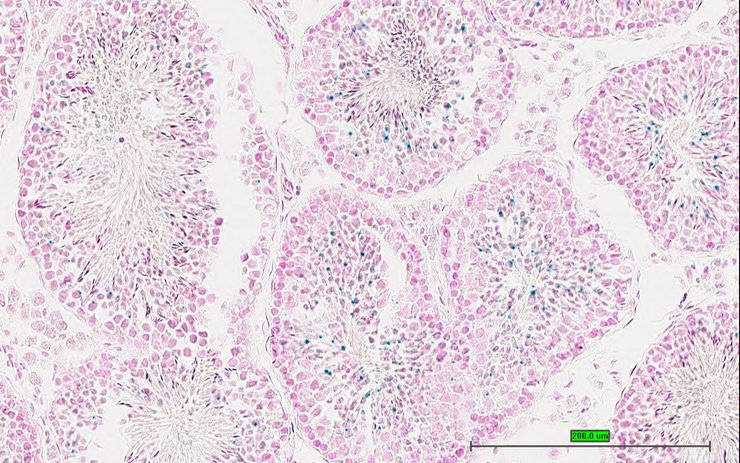

TS28: testis Present UC Davis_1873633

Specimen UC Davis_1873634: postnatal adult; Gdap1tm2b(KOMP)Wtsi/Gdap1+ (more )

Structure Level Pattern Image Note

TS28: testis Present UC Davis_1873634